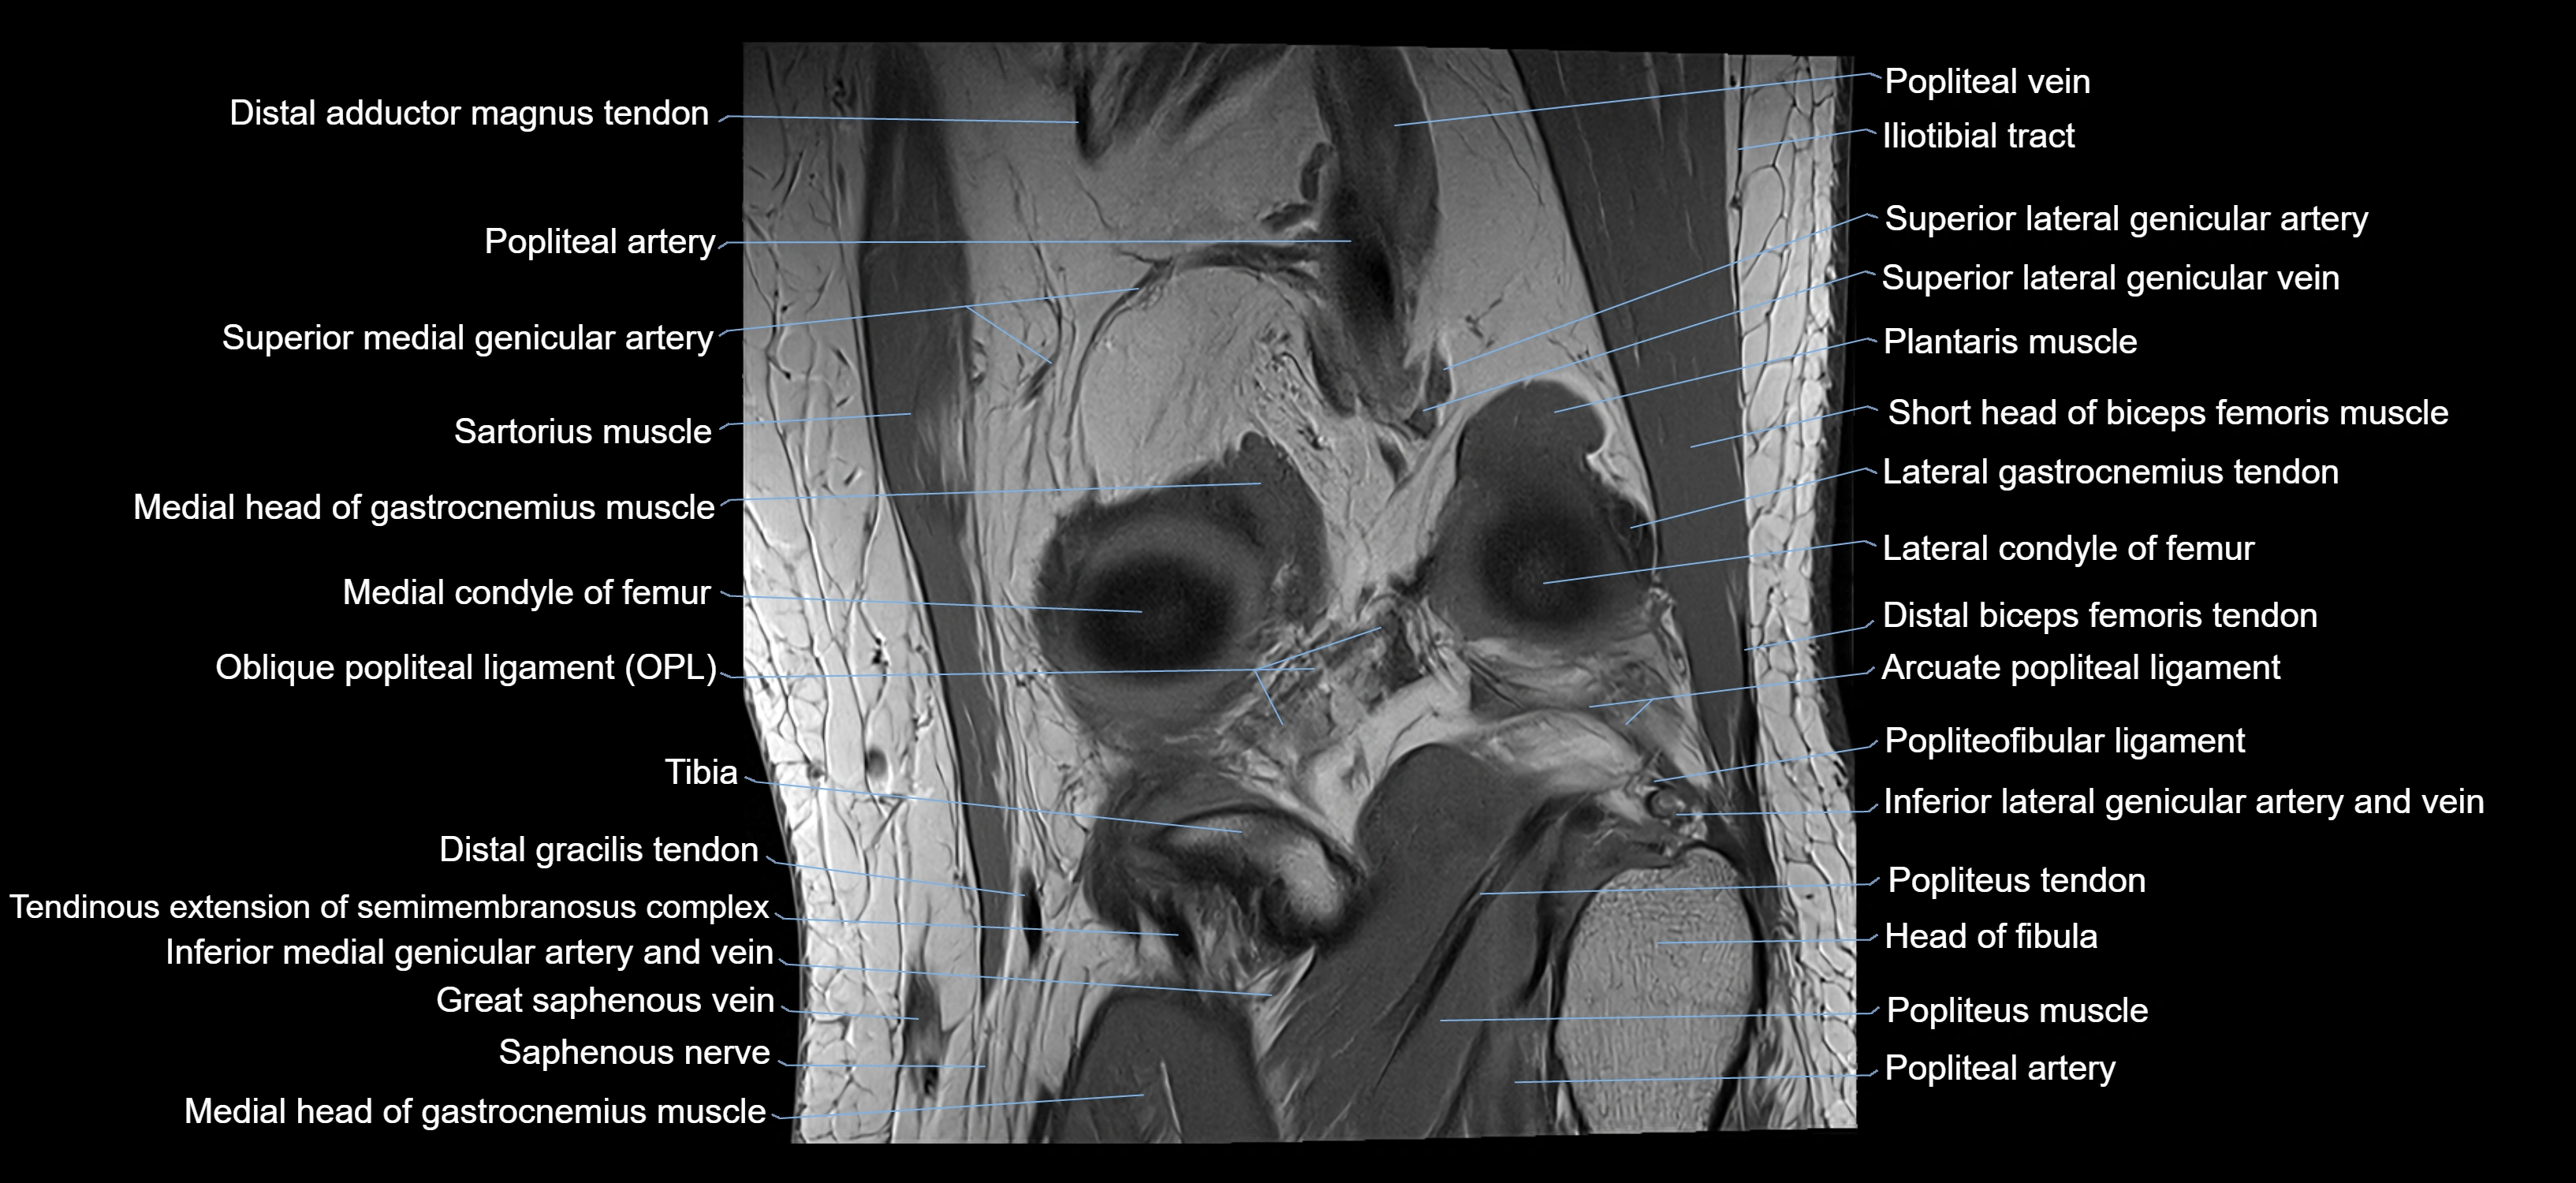

- Arcuate popliteal ligament

- Distal biceps femoris tendon

- Head of fibula

- Lateral gastrocnemius tendon

- Lateral head of gastrocnemius muscle

- Medial head of gastrocnemius muscle

- Oblique popliteal ligament

- Popliteal artery

- Popliteal vein

- Popliteus muscle

- Popliteus tendon

- Saphenous nerve

- Sartorius muscle

- Sartorius tendon (Distal)

- Semimembranosus muscle

- Soleus muscle

- Superior lateral genicular artery

- Superior lateral genicular vein

- great saphenous vein